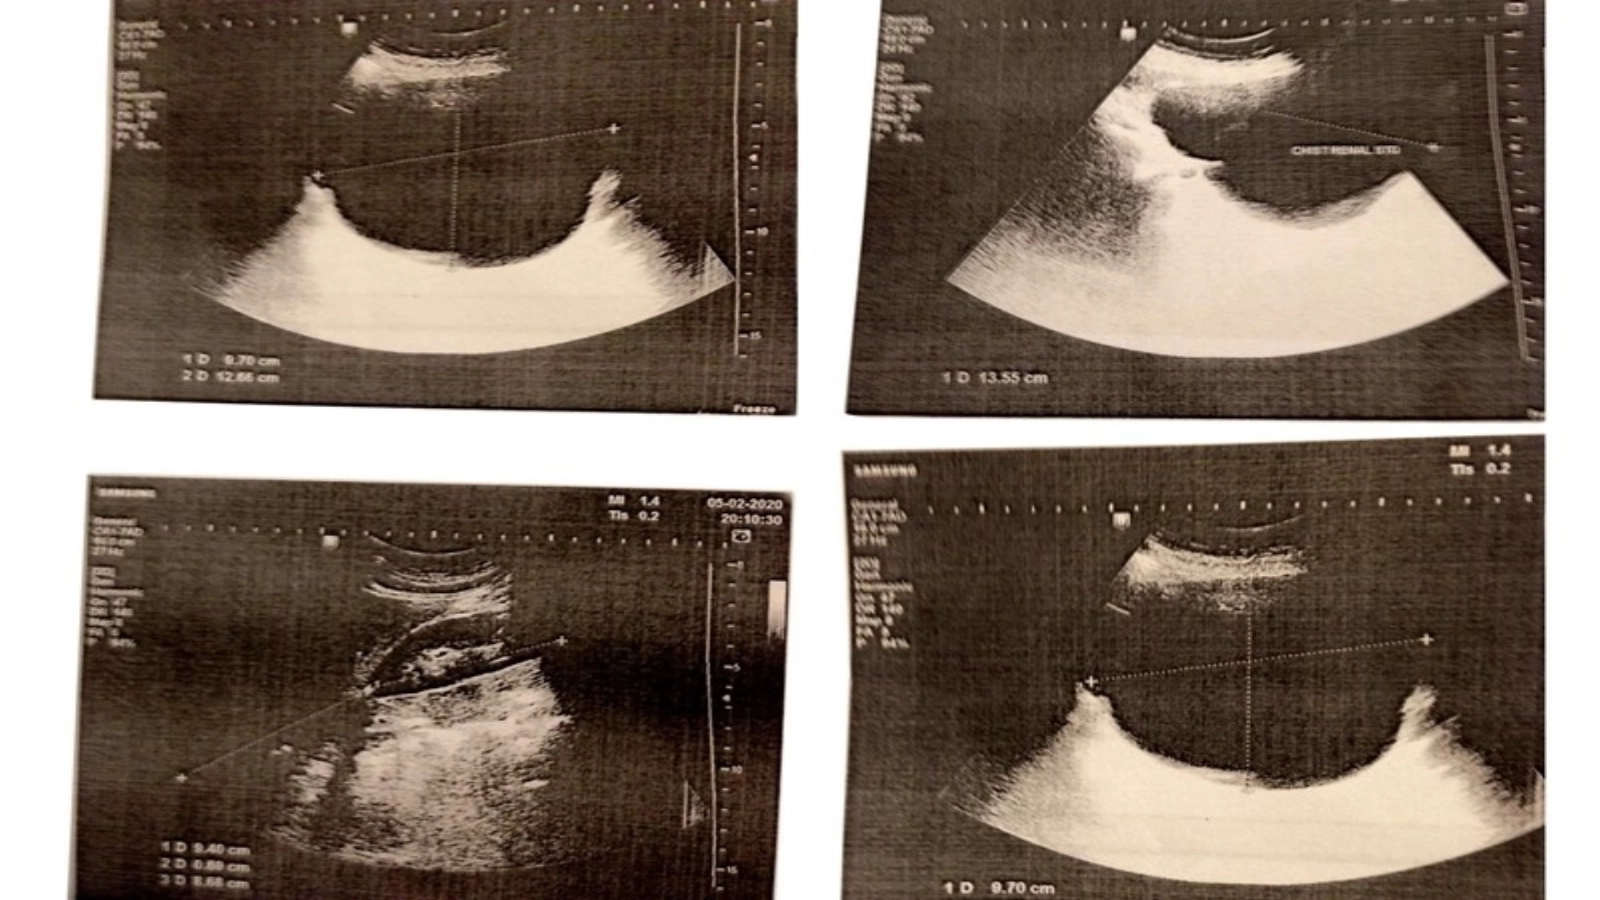

"A acaparat încet dar sigur un spațiu atât de mare încât a deplasat organul în jos 7 cm. Nu mă durea, dar consecințele puteau fi grave, ajunsese la 13 cm în diametru. Îngrijorarea nu îmi dădea pace, cu toate că evoluția sa a fost supravegheată zilnic", ne spune doamna Melinte. Concomitent, pacienta era diagnosticată și cu o formațiune tumorală ovariană.